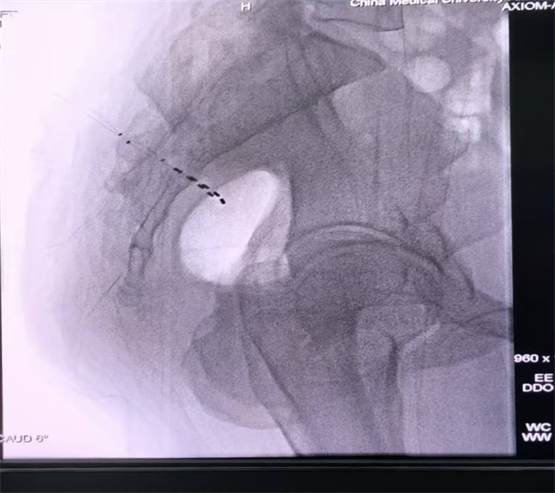

治疗分为两个阶段进行。团队首先为患者实施了一期双侧骶神经调控电极植入术。术中在DSA引导下将电极精准植入双侧S3神经孔,术中应答良好。术后随访显示,患者排尿功能得到改善,单次排尿量可达约200ml,尿动力学检查显示排尿期可见逼尿肌主动收缩。

术中电极位置图